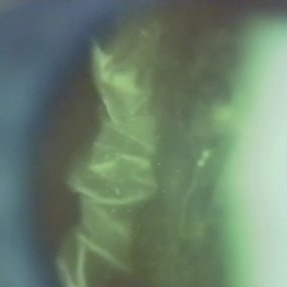

Slit lamp (video) image showing folds in the posterior vitreous cortex in an eye with PVD.

Photographer: Martin Snead, MD, Cambridge, England

Condition/keywords: folds, posterior vitreous cortex, PVD, vision degrading myodesopsia, vitreous